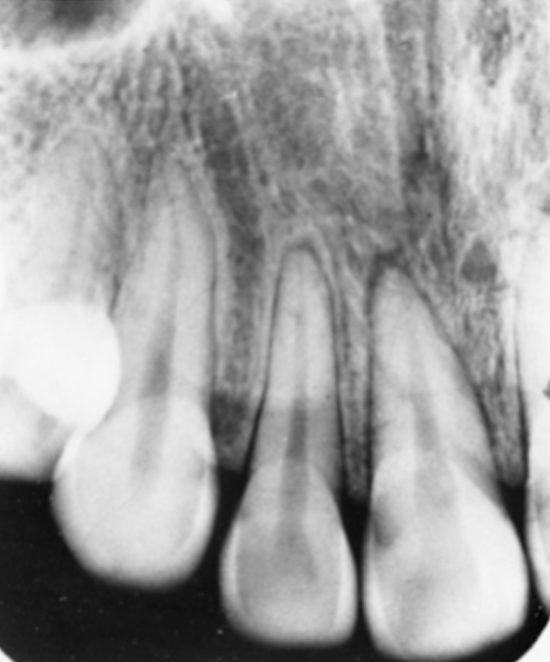

there may be no radiographic changes

tooth may have widened PDL space

pulp space may greatly reduce in size or disappear after months or years

if a young tooth devitalizes due to concussion, pulp space may remain wider than other teeth as the patient ages

if the pulp space of one tooth is a different size than surrounding teeth, suspect a non-vital tooth